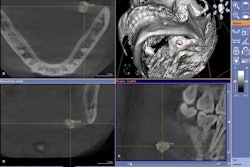

A total of 72 sites on 25 human teeth with various degrees of natural demineralization were analyzed. Continuous evaporation of water inside the pores by pressurized air-drying produced a thermodynamic response on the tooth surface, the researchers noted. The temporal profile of the temperature depends on the amount of water at each position, so they examined this in relation to the degree of porosity and the lesion severity.

Using this approach, the researchers found a detection sensitivity of 77% and specificity of 87% for areas that were sound or had a histological E1 lesion, 87% sensitivity and 72% specificity for areas that had either an E2 or enamel-dentin junction lesion, and 58% sensitivity and 83% specificity for areas with a lesion reaching the dentin.